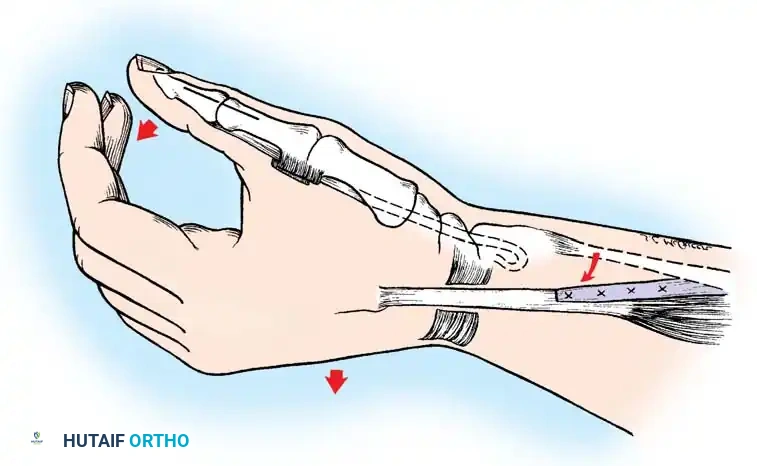

For most authors, the ultimate goal of distal upper extremity reconstruction in tetraplegia is to obtain a reliable key grip (lateral pinch). Key pinch posture provides a stronger, broader gripping surface, is cosmetically preferable, and is biomechanically easier to achieve than a "chuck-jaw" (three-jaw chuck) pinch.

The Tenodesis Effect

In patients lacking active finger flexion, the natural tenodesis effect of the wrist must be harnessed. When the wrist is actively extended (via ECRL/ECRB), the extrinsic finger flexors (FDP, FDS) and the flexor pollicis longus (FPL) passively tighten, causing the fingers and thumb to flex and pinch against each other.

Moberg Key Grip Procedure

For Group 1 or Group 2 tetraplegics, the Moberg key grip procedure is foundational. This involves:

1. FPL Tenodesis: The FPL tendon is divided proximally and anchored to the distal radius. As the patient actively extends the wrist, the anchored FPL passively tightens, driving the thumb into lateral pinch against the index finger.

2. Thumb CMC Arthrodesis or Stabilization: To prevent the thumb from collapsing into retropulsion during pinch, the carpometacarpal (CMC) joint is often arthrodesed, or the metacarpophalangeal (MCP) joint is stabilized via capsulodesis or arthrodesis.

- Brachioradialis (BR) to FPL Transfer: The BR is an excellent donor for the FPL. It has immense power and adequate excursion. The BR must be mobilized extensively, proximal to the elbow joint, to maximize its amplitude.